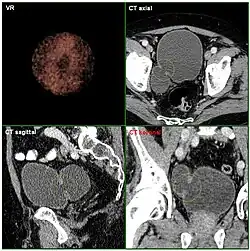

- Divertikel des Darmes (Darmdivertikel)[1] sind vorwiegend im Dickdarm (insbesondere im Sigmoid) anzutreffen. Sie entstehen durch einen Prolaps der Schleimhaut durch die Muskellücken der Darmwand, sind also meistens Pseudodivertikel. Diese Muskellücken sind eigentlich Durchtrittsstellen der Darmwandgefäße und stellen somit einen Prädilektionsort für die Divertikelbildung dar. In einigen Fällen kann das Divertikel zunächst intramural (innerhalb der Darmwand) verlaufen, im späteren Verlauf nimmt die Ausstülpung der Schleimhaut an Größe zu und die Divertikel können symptomatisch werden. Häufig ist dies der Fall im höheren Lebensalter (> 60 Jahre). Als Ursache der Schleimhautausstülpung wird ein erhöhter Darminnendruck (= intraluminaler Druck) vermutet, der wiederum durch einen zu geringen Ballaststoffgehalt der Nahrung entstehen soll. Eine aktuelle Studie konnte jedoch keinen Schutzeffekt durch einen hohen Ballaststoffgehalt nachweisen.[2] Rektumdivertikel sind beim Menschen äußerst selten, kommen aber beim Hund, insbesondere im Zusammenhang mit einer Perinealhernie, häufiger vor.[3]